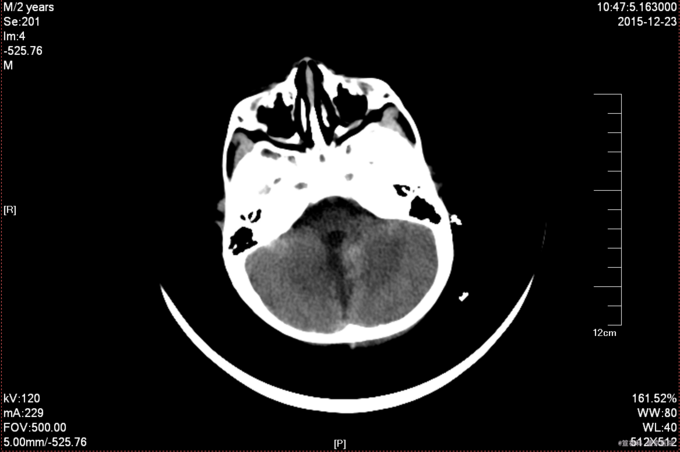

患儿,2岁,以“突发恶心、呕吐10天”为主诉入院 现病史:患者10天前不明原因出现恶心、非喷射性呕吐多次胃内容物,家属急送当地医院就诊,曾以胃肠型感冒就治,给予阿米卡星,西咪替丁等药物治疗,具体剂量不详,因症状不能缓解,于今日16时行头颅CT检查,提示:考虑小脑蚓部髓母细胞瘤伴梗阻性脑积水及脑室周围间质水肿(丹东东港市中心医院 2015年12月19日)。患儿,无意识丧失,无发热抽搐,无视力丧失,四肢活动可,家属为求进一步诊治来我院,门诊以四脑室占位性病变为诊断收入院,病来患儿纳差,嗜睡,大小便正常,发病来体重较发病前减少1公斤。 3.既往史与过敏史:患儿无先天性心脏病;否认肝炎结核病史、否认糖尿病病史,否认输血史;否认青霉素及头孢类药物过敏史。按规定计划免疫。

查体: T:36.5℃,P:100次/分,BP:96/60mHg,R:16次/分,嗜睡状态,查体合作。粗测双眼视力下降。双瞳孔等大正圆,D≈3.0mm,对光反射灵敏,眼球向各方向活动自如,眼位居中,无眼震。面纹对称,无张口受限,伸舌居中,悬雍垂居中。四肢活动自如,肌力IV级,肌张力正常,深浅感觉检查未见异常。双巴氏征(-). 辅助检查:头颅CT检查(丹东东港市中心医院 2015年12月19日):考虑小脑蚓部髓母细胞瘤伴梗阻性脑积水及脑室周围间质水肿。